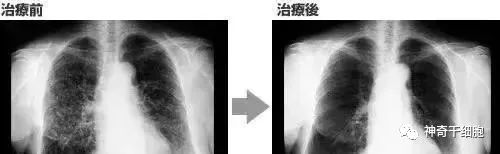

案例3:一名广泛期小细胞肺癌患者,在进行4个疗程化疗和4次高度活化NK细胞回输后,患者第一次进行治疗后的CT复查,结果显示,肿瘤缩小到了原来的1/8。而且距发病第六年的CT复查中,仍旧没有发现任何异常及复发的迹象。